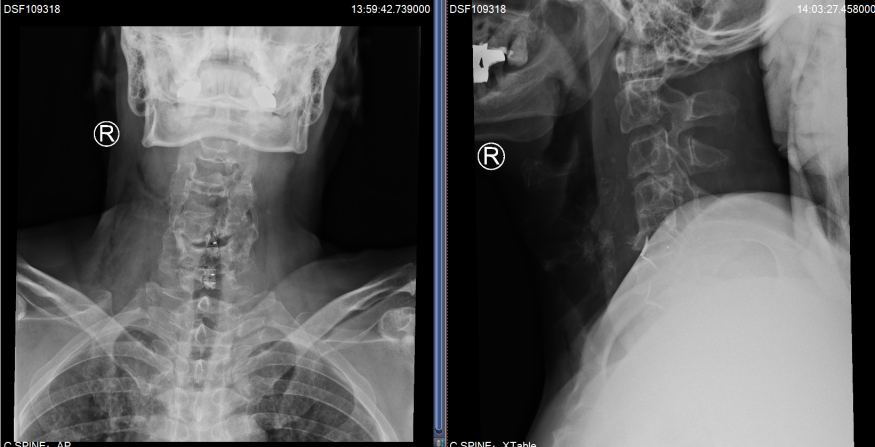

就这样,2022年3月,Hester办理了住院手续,在进一步的详细评估后,姜主任制定了经前路减压融合术的手术方案。与后路椎管扩大成型术相比较,具有创伤小、直接减压与恢复快的优点。但由于Hester颈椎的先天畸形与严重的骨质增生,手术难度却增加了很多。手术当天,在麻醉科医生黎鹏与手术室护士的密切配合下,姜为民主任带领王喜安副主任和赵星毅博士,经过两个多小时的精雕细琢,将增生的骨赘在狭窄变形的椎间隙里一一切除,解放了受压的脊髓,完成了这台特殊的“颈椎前路椎间盘切除+椎间融合术”。Hester在术后第一天就激动地告诉姜主任:“Right after the surgery I found the balance problem was gone. I can stand again on one leg without crashing on the floor now and the numbness in the finger is reduced.”(我右手持续了3年之久的麻木感已经明显缓解,佩戴颈托后试着下床行走,发现术前那种失去平衡的症状不见了,甚至单足站立也不怕摔倒)。

术后复查X片,C5/6和C6/7椎间隙高度恢复满意